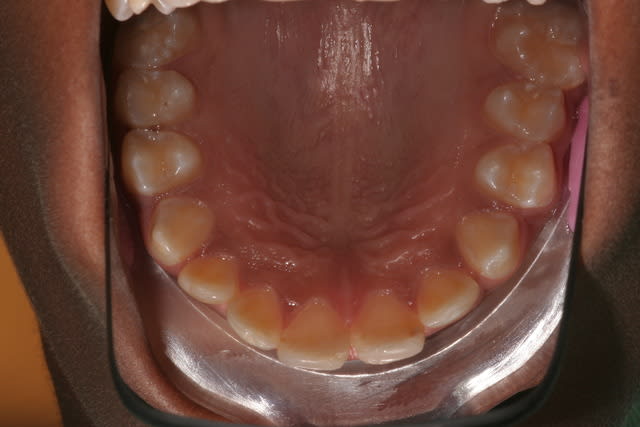

pr apporter de l'eau au moulin de la non conservation des 6 cariées,necessitant TR

extraction des 6 à 9 ans(MIH sur les 6 detruites et 11/21 qui on été refaites en compos)

photos à 12

ce n'est pas parfait à la mandibule mais acceptable car le père n'a pas souhaité faire le ttt odf

à 12 ans il te faudra vraiment convaincre pr l'odf